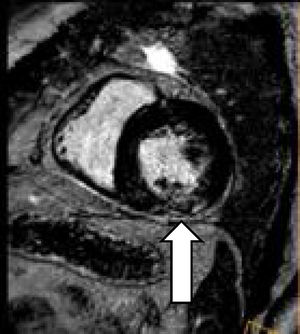

Observación clínicaUn varón de 48 años, sin hábitos tóxicos ni antecedentes de interés ingresa por cefalea, parestesias en la extremidad superior derecha y crisis hipertensiva. TC craneal: sin alteraciones. Se inicia tratamiento vasodilatador, diurético y antiagregante plaquetario con buen control de las cifras tensionales y desaparición de la focalidad neurológica. En la RX de tórax se aprecia redistribución vascular e hilio derecho aumentado de tamaño. Se realiza TC toracoabdominal que muestra múltiples adenopatías de tamaño valorable, entre 10 y 20mm a nivel intratorácico (en el espacio prevascular, subcarinales, pretraqueales derechas, hiliares bilaterales y adyacentes a bronquio inferior izquierdo), sin alteraciones en el parénquima pulmonar ni a nivel abdominal. Se practica broncoscopia, sin alteraciones, y 3 PAAF ganglionares con abundante celularidad linfoide sin atipias. Las baciloscopias y el cultivo para micobacterias resultan negativos. Un ecocardiograma transtorácico muestra: ventrículo izquierdo con moderada dilatación de su cavidad, ligera hipertrofia concéntrica y moderada reducción de su contractilidad global por acinesia inferior e hipocinesia del resto de segmentos. FE estimada 37%. Disfunción diastólica de tipo restrictivo sugestiva de aumento de presión capilar. Moderada dilatación de la aurícula izquierda. La cardiorresonancia magnética (CRM) muestra:

Patrón parcheado intramiocárdico ediobasal inferolateral y basal inferior y lateral del ventrículo izquierdo sin necrosis, sugerente de sarcoidosis versus enfermedad de Fabry (fig. 1).

Se cursa una muestra de gota seca (blood-spot) que descarta enfermedad de Fabry, y se realiza nueva PAAF ganglionar, por ecobroncoscopia, que muestra material hemático y linfocitos sin atipias ni granulomas. Las baciloscopias y el cultivo para micobacterias fueron negativos. Una coronariografía no objetiva lesiones angiográficas significativas. Una gammagrafía con galio muestra captación en la región mediastínica alta anterior derecha e izquierda, que orienta hacia un origen inflamatorio, sin descartar un proceso linfoproliferativo. La analítica general, incluida la determinación de inmunoglobulinas totales, enzima conversora de la angiotensina, determinación de autoanticuerpos y serologías viricas resultaron negativas o normales.